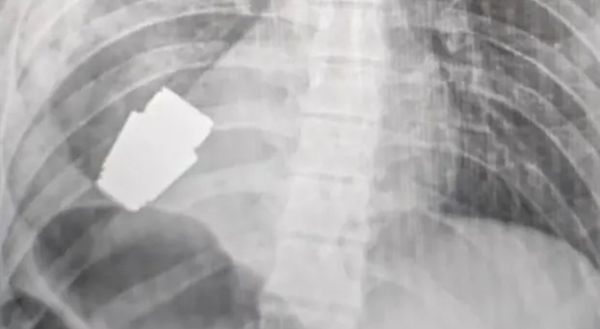

ഹൃദയത്തിന് തൊട്ടുതാഴെ ഗ്രനേഡ്; സര്‍ജറിയിലൂടെ യുക്രൈന്‍ സൈനികന്‍ അത്ഭുതകരമായി രക്ഷപെട്ടു

വിജയകരമായ ഒരു അസാധാരണ ശസ്ത്രക്രിയയിലൂടെ യുക്രൈനിയന്‍ സൈനികന്റെ നെഞ്ചില്‍ നിന്നും ഒരു ഗ്രനേഡ് പൊട്ടാതെ പുറത്തെടുത്തു. ഏത് നിമിഷവും പൊട്